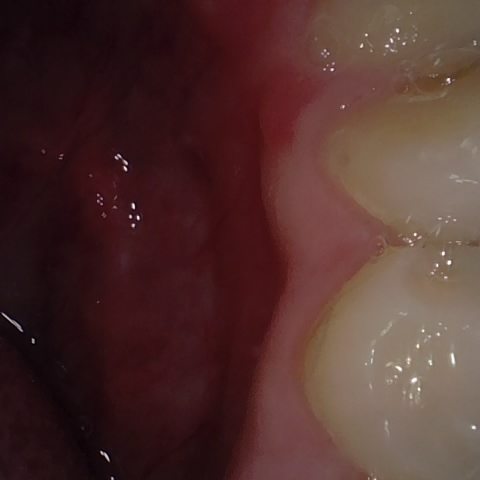

Image 281 / 400

NHD20738

Annotated as "Bad"

Original Image Rendering Image